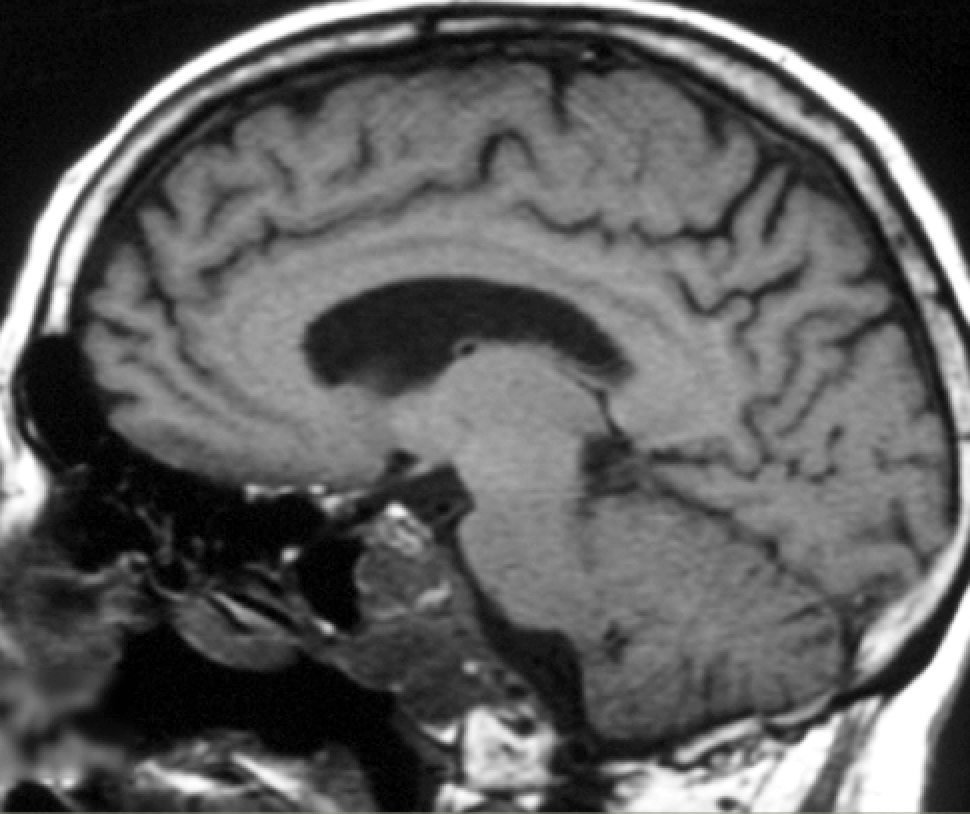

48 yo with subacute myelopathic symptoms (heavy feeling in legs that improves with rest, difficulty standing, paresthesias, urinary symptoms, back pain)

Diagnosis and eponym?

Spinal cord dural AVM

Foix-Alajouanine syndrome

Intradural Serpentine flow voids along surface of spinal cord

Angiogram: Enlarged draining vein

Spinal cord: Diffuse hyperintense T2 intramedullary signal

Symptoms due to venous hypertension

(Note: If blood vessel flow voids appear to be in subarachnoid space and angiogram shows a fistula, then consider spinal dural AV fisula)